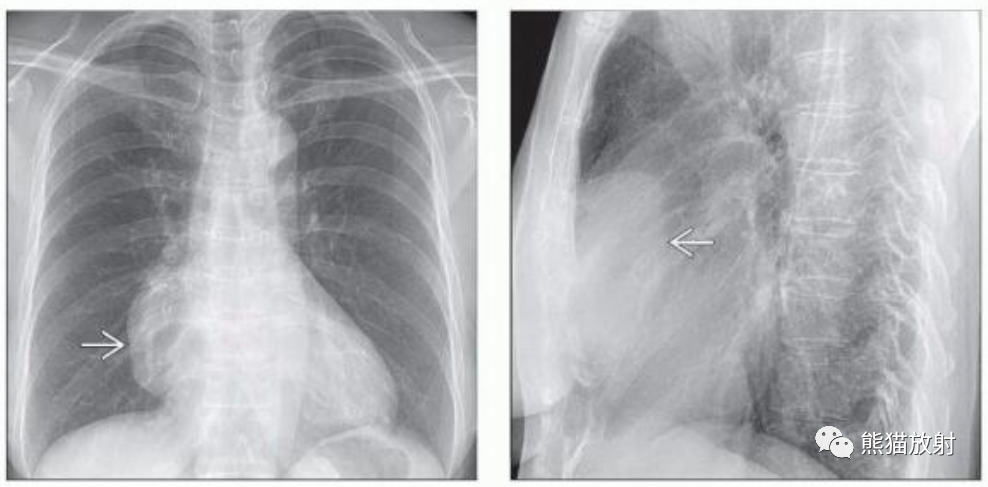

(左) 胸腺瘤患者的胸片显示纵隔偏右侧肿块(箭),边界清楚,轻度分叶。在正位胸片上胸腺瘤常表现为纵隔轮廓异常。

(右) 同一病人的侧位胸片显示肿块位于前纵隔。侧位胸片可以定位纵隔肿块的分区。